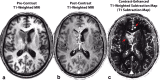

Radiographic endpoints including response and progression are important for the evaluation of new glioblastoma therapies. The current RANO criteria was developed to overcome many of the challenges identified with previous guidelines for response assessment, however, significant challenges and limitations remain. The current recommendations build on the strengths of the current RANO criteria, while addressing many of these limitations. Modifications to the current RANO criteria include suggestions for volumetric response evaluation, use contrast enhanced T1 subtraction maps to increase lesion conspicuity, removal of qualitative non-enhancing tumor assessment requirements, use of the post-radiation time point as the baseline for newly diagnosed glioblastoma response assessment, and "treatment-agnostic" response assessment rubrics for identifying pseudoprogression, pseudoresponse, and a confirmed durable response in newly diagnosed and recurrent glioblastoma trials.